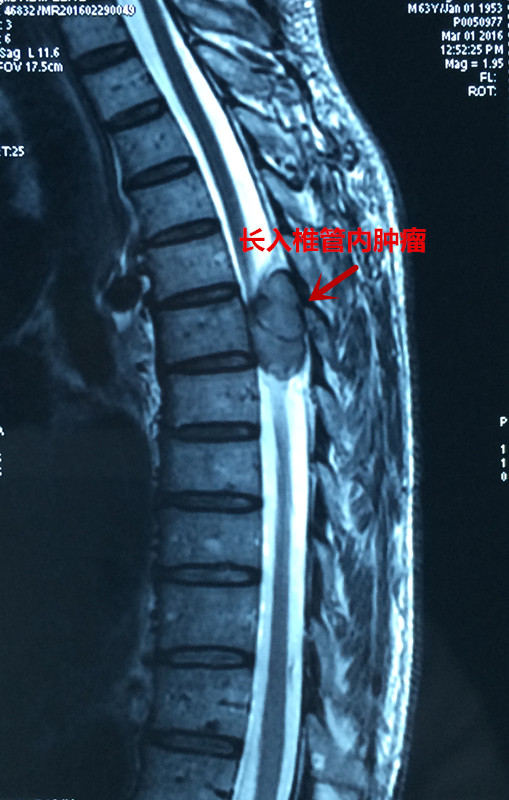

患者彭某,男,63岁,以胸背部疼痛5年,双下肢无力麻木半年之主诉入院,5年前无明显原因出现胸背部疼痛,影响夜休,就诊于当地医院,给与对症治疗,效果欠佳,背痛逐渐加重,长期服用非甾体类止痛药止痛,半年前无明显原因出现双下肢麻木、无力,走路不稳,进行性加重,未做治疗,2016年3月初就诊于当地医院,行胸椎MRI:胸6椎体水平椎管内外实质性暂未并胸6椎体附件、右侧第6肋骨骨质破坏,考虑恶性肿瘤可能,全身骨显像提示胸6椎体及右侧第6肋骨代谢异常活跃,恶性病变可能性大。当地医院拒绝治疗,为求进一步诊治,来我院门诊以“脊柱肿瘤”之诊断收入院。发病来食纳差,睡眠可,大小便正常,体重无明显变化。专科情况:脊柱生理弧度可,胸6棘突及附件压痛叩击痛阳性,半双下肢抽痛,双下肢肌张力可,肌力约3级,平乳头以下肢体感觉减退,无汗,双侧膝腱反射及跟腱反射阴性,双侧巴氏征阴性,左侧踝阵挛阳性。

患者入院后,王栋副主任,李锋涛主治医师高度重视,仔细询问患者病情,进行专科查体,分析以往患者的影像学资料,由于肿瘤组织生长巨大,严重压迫右肺,并且已经破坏了胸6椎体及其附件、右侧第6肋骨等,局部结构复杂,为了帮助手术方案的设计,我们采用3D打印技术,术前将肿瘤局部解剖结构打印成3D模型。邀请胸外科张维教授多次会诊,根据3D打印模型制定了详细的手术计划及围手术期治疗方案。经过严密的手术前准备,以王栋副主任、张维教授为主刀、李锋涛主治医师为助手,吴刚副主任医师、罗斌医师为麻醉医师,殷敏、马霞为配合护士,黄亚娟、王芳医师为术中诱发电位监护医师的手术团队努力下,手术顺利完成,成功切除了胸腔内、椎体旁及椎管内肿瘤组织,并进行了脊柱的重建。术后患者恢复良好,很快下肢感觉、肌力恢复,现患者正在康复中。